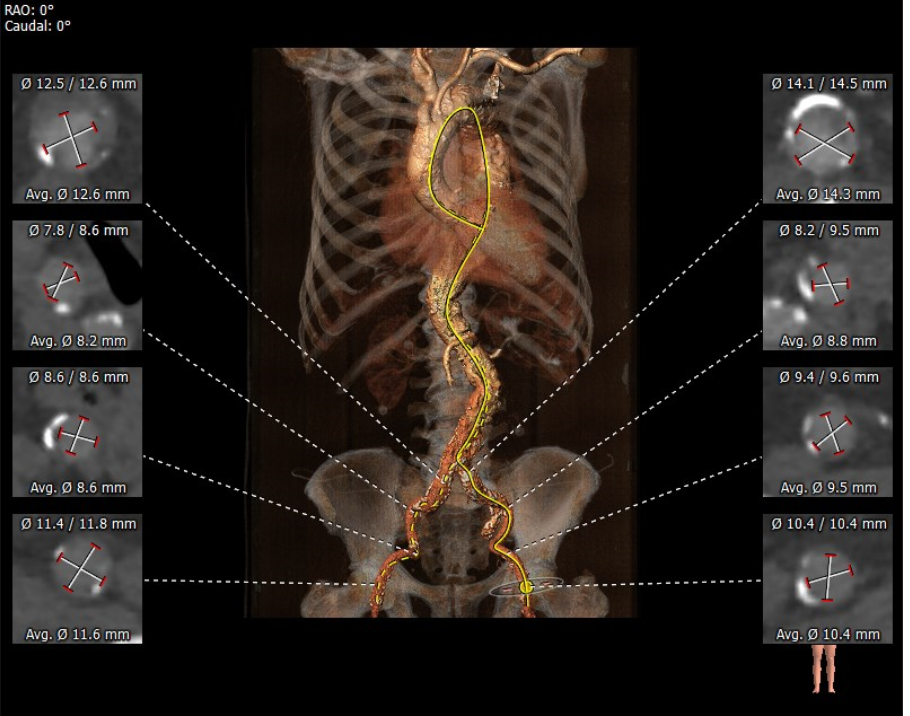

外周分析

• 该患者外周多发附壁血栓,合并胸主、腹主及髂总动脉瘤,动脉瘤巨大,并且内由附壁血栓,经股动脉行TAVR手术血管并发症风险极高。测量发现双侧锁骨下动脉内径可,预计采用左锁骨下动脉为主入路,右股动脉为辅入路。